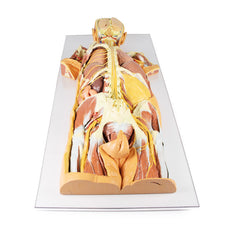

With the specimen cut in a sagittal plane in line with the cardiac impression, nerves and lymphatics are difficult to identify however the groove from the oesophagus as it descends posteriorly to pierce the diaphragm can be seen alongside the cardiac impression (of the right atrium) is notable anterior to the hilum of the right lung; the right main bronchi and its subsequent divisions into lobar bronchi, found in this specimen more posterior in the hilum; he pulmonary artery and its divisions, located most superior within the hilum; the superior and inferior pulmonary veins and their divisions which are most inferior and anterior in the specimen. the oblique and horizontal fissures along the lateral surface of the specimen and the Hilar lymph nodes around the hilum on the medial surface of the lung.

The diaphragmatic surface is found inferiorly and the costal visceral surface is on the posterior of the specimen.